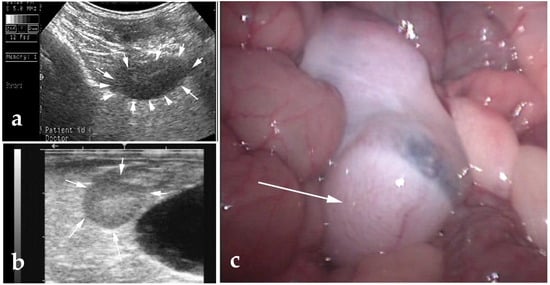

6.1. Scrotal Enlargement

- Ram, S.M.T.; Satija, K.C.; Chauhan, R.S. Orchitis in a Camel (Camelus dromedarius) Infected with Sarcoptes Cameli. Vet. Parasitol. 1987, 23, 307–309. [Google Scholar] [CrossRef]

- Aubry, P.; Swor, T.M.; Löhr, C.V. Septic Orchitis in an Alpaca. Can. Vet. J. 2000, 41, 704–706. [Google Scholar]